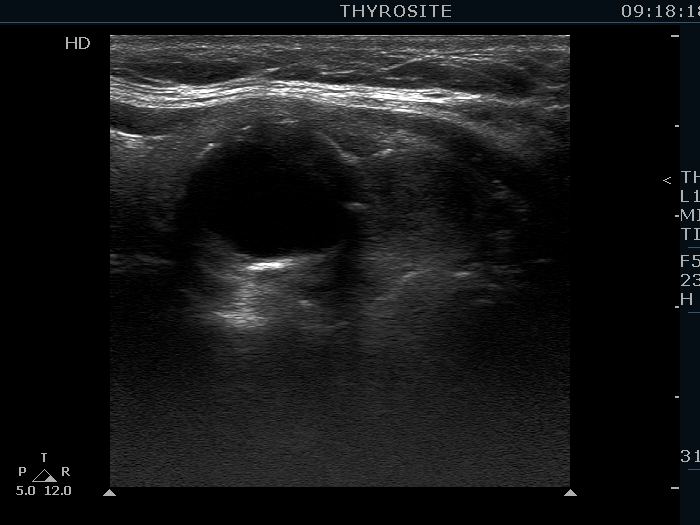

Benign hyperplastic nodule (histological diagnosis) - case 489 |

The nodule had an eggshell calcification.